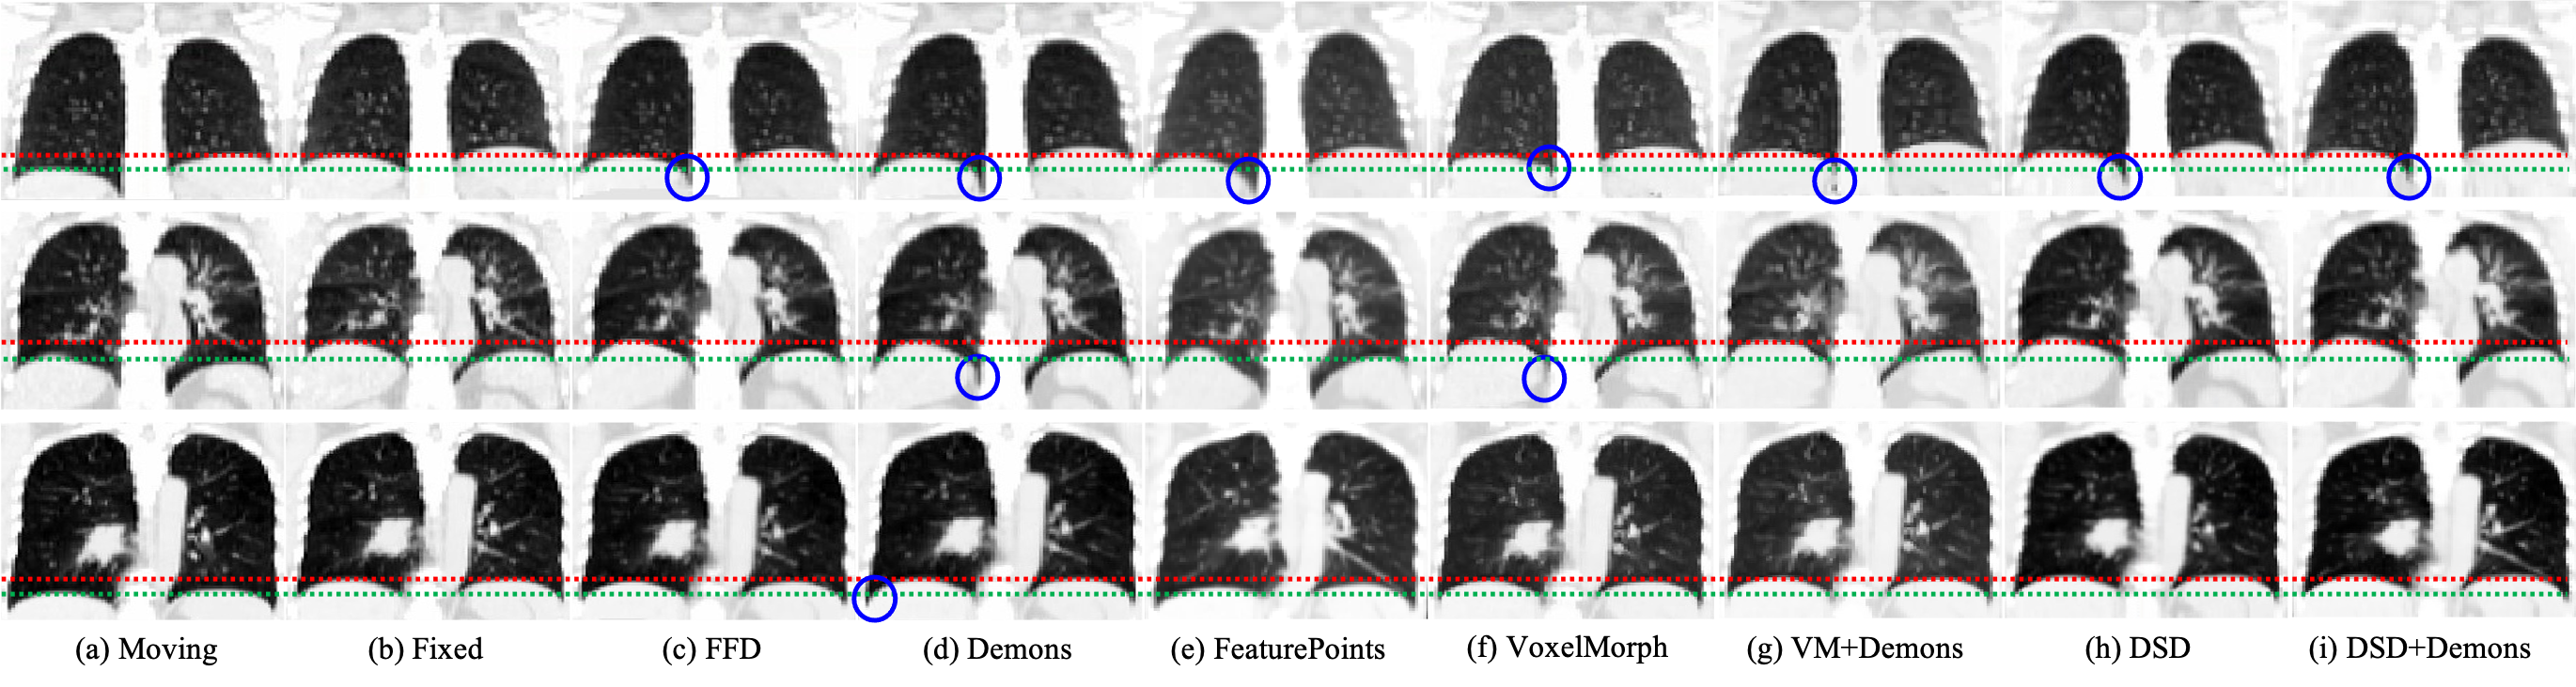

Refer to caption

Figure 9: Visual results of three samples from 4D-L-CT. The red line and green line describe the position of the right diaphragm (in anatomy) at the end of expiration and the end of inspiration respectively. The blue circle indicates the horizontal over-squeezing regions where should move upward.

V-A2 4D-L-CT dataset

Table II lists the quantitative motion estimation results on the 4D-L-CT dataset. Similar to the evaluation of cardiac data, we also compare the results with respect to different time intervals between the two input time-points. Our method DSD + Demons achieves the best registration accuracy. In fact, the performance of all the compared methods is similar on the 4D-L-CT dataset with only 0.01 difference in DSC between the highest (DSD + Demons: DSC=0.982, HD=4.85) and the lowest (VoxelMorph: DSC=0.972, HD=5.06). This is because the anatomical structures of the lungs are relatively simple, and the motion is easy to estimate compared to the cardiac structure.

Fig. 9 depicts the warped outputs for all the methods. The temporal changes of lungs in the appearance and shapes are generally mild between the phases of maximum breath holding and minimum exhalation (c.f., green lines and red lines in Fig. 9). Although the conventional method Demons achieves a well quantitative performance, there is unfortunately an over-squeezing in the deformation, and thus artifacts appear in the deformed image. For instance, as indicated by the blue circle in Fig. 9, the estimated deformation on the lower lobes of the lungs is horizontally over-squeezed, where the correct deformation (see the fixed image and the moving image in Fig. 9) should have been an upward movement. In contrast, our proposed method is able to effectively reduce the error of motion estimation in the stenosis of the lower lobe of the lung.